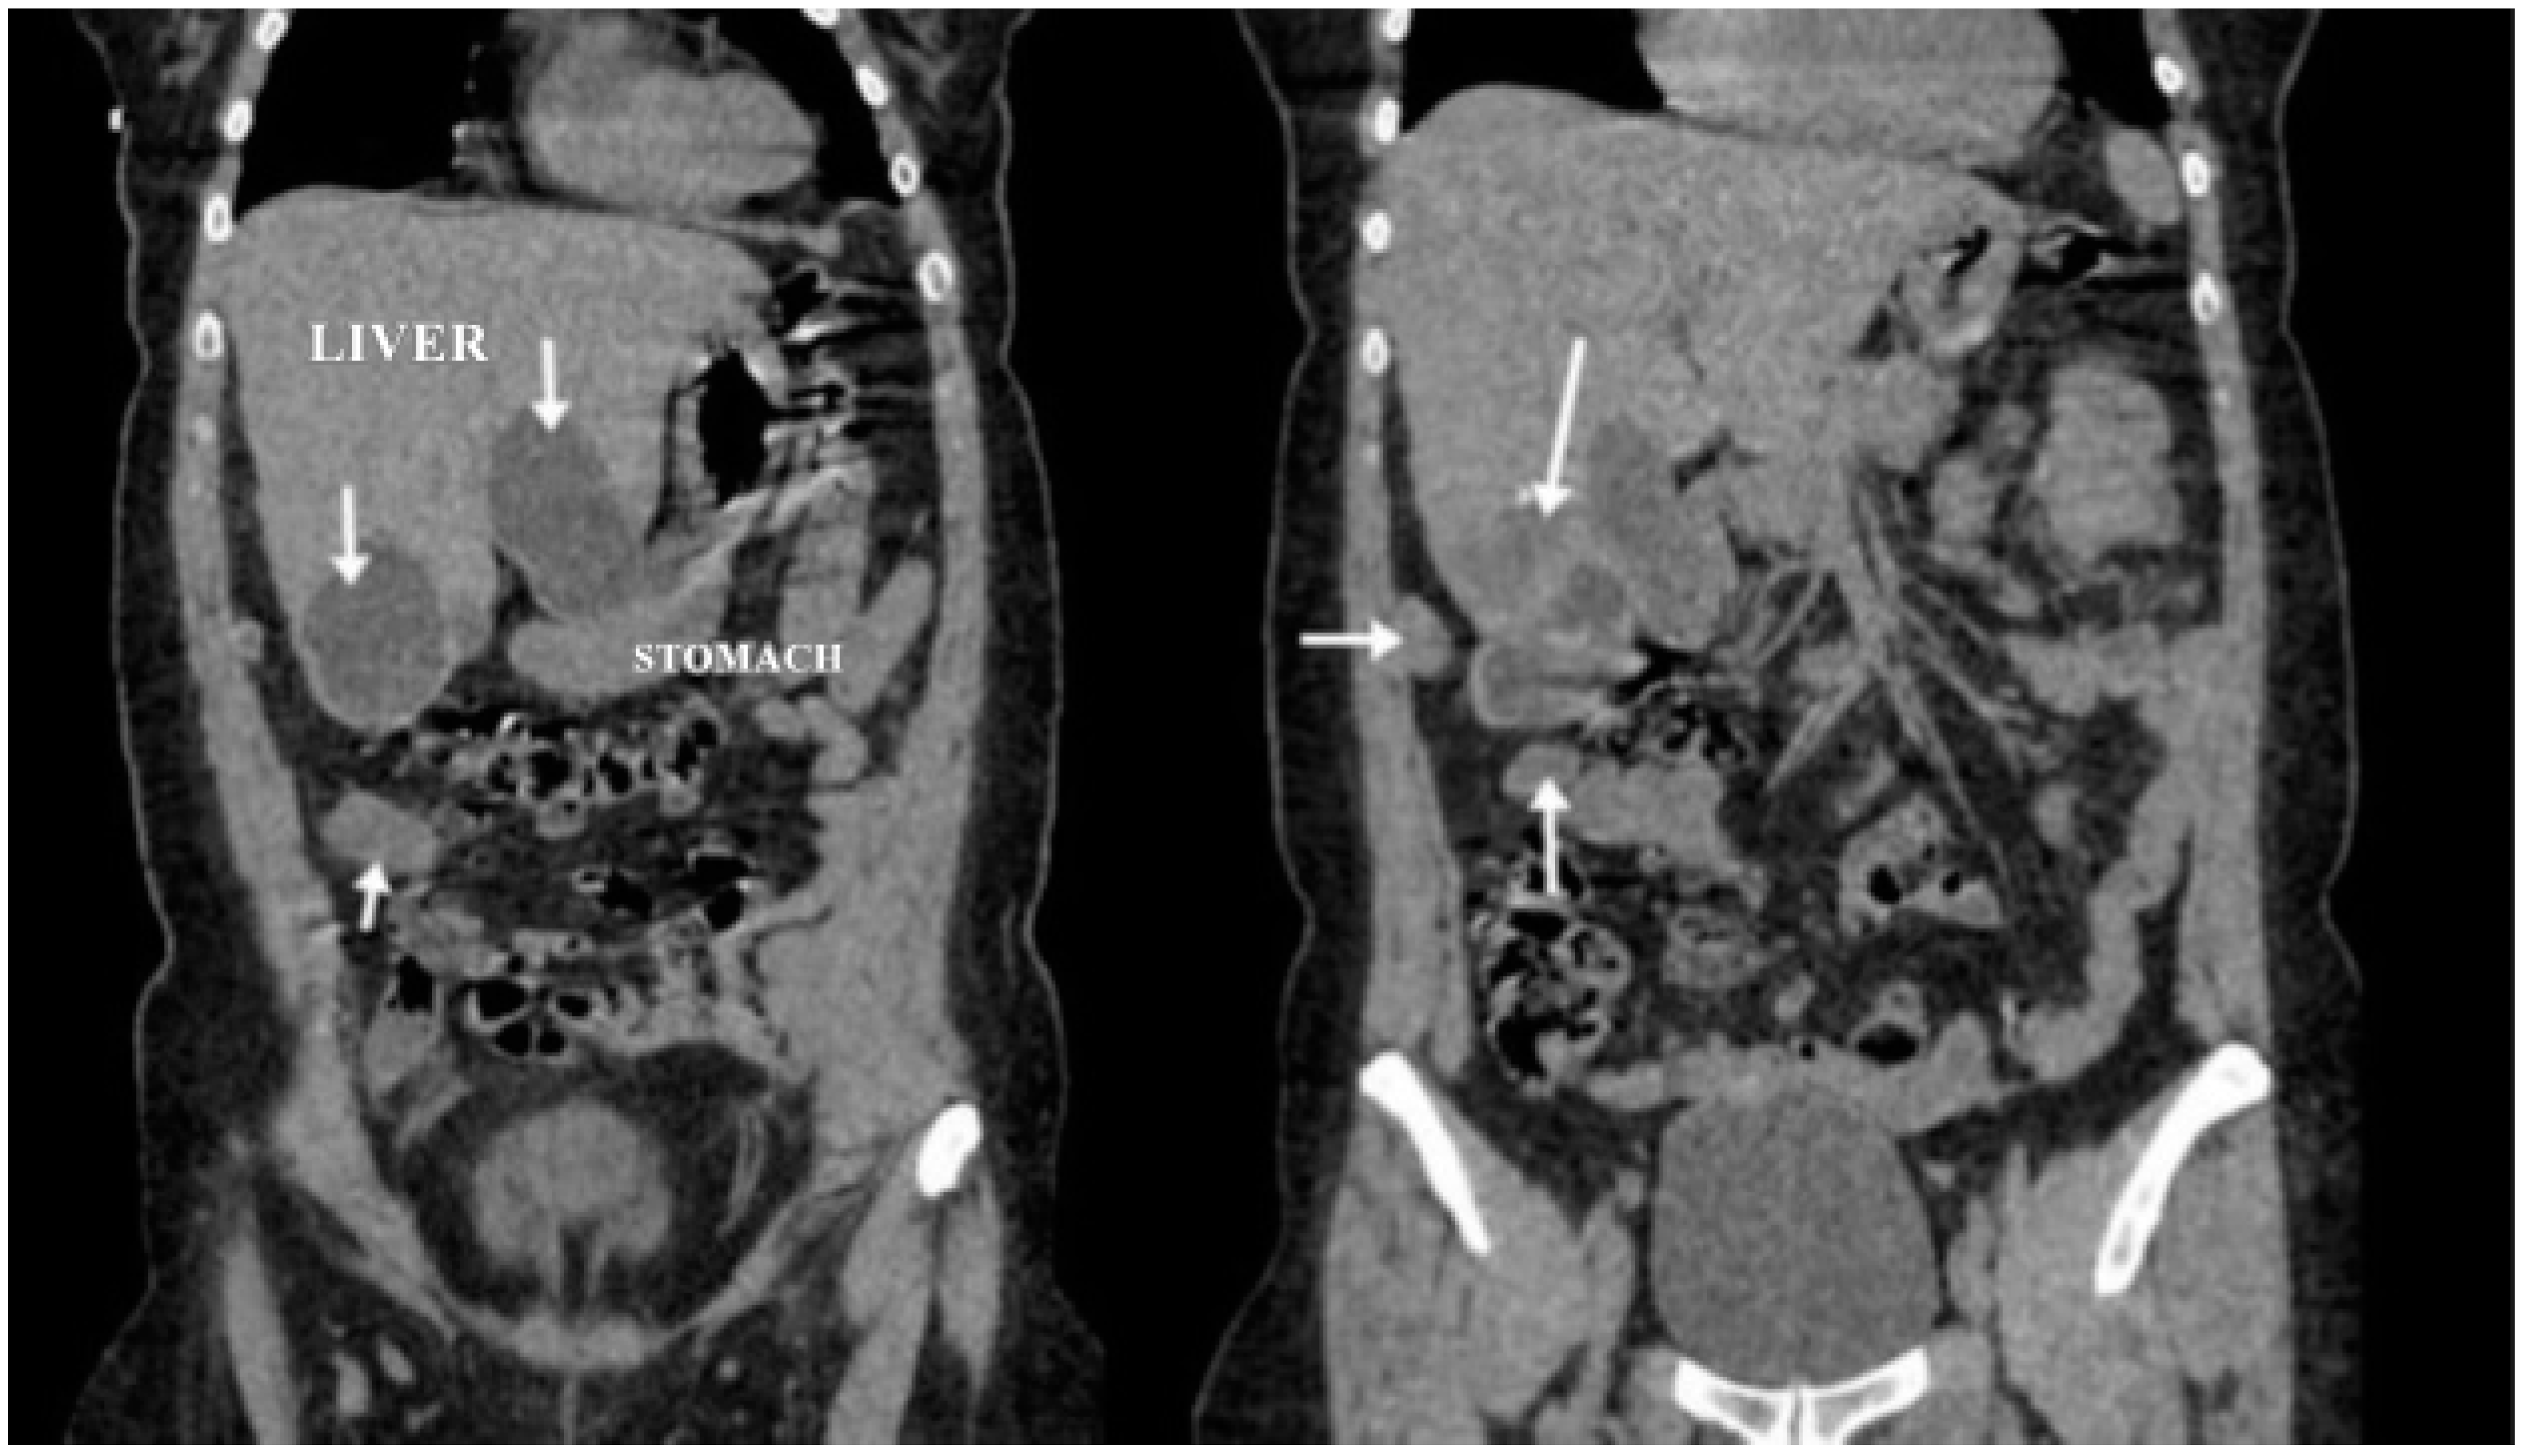

A CT examination revealed multiple cystic images in the hepatic segments V, VI, and VII, with subhepatic extension and involvement at the fissures of the venous ligament. Cystic images were also observed in the anterior abdominal wall and submesocolic (Figure 5, Figure 6, Figure 7, Figure 8 and Figure 9). Blood tests showed no significant abnormalities, and ELISA determination of IgG class antibodies to Echinococcus granulosus was positive at 1.66 IV (with values considered negative at ≤0.9 IV and positive at ≥1.1 IV).

The imaging highlights hepatic cysts in segments V, VI, and VII, a large cystic formation in the round ligament, a cyst in the parietal peritoneum, two cysts in the greater omentum, and two cysts located in the submesocolic enteral mesentery.

Figure 3. Liver and round ligament hydatid cysts (indicated by arrows).

Figure 7. Coronal section (liver, round ligament, mesenteric, omental, and peritoneal hydatid cysts indicated by arrows).